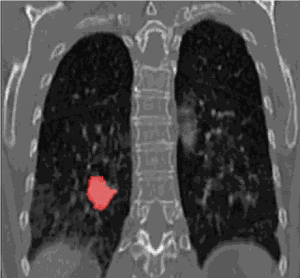

无独有偶,我们还发现了一张美国的肺癌死亡率趋势图。

两根曲线的变化频率,惊人的相似,只是:死亡率曲线向后延迟了大约20年,这不禁让人细思极恐。

大量的吸烟者,都在20年后陆续死亡了。